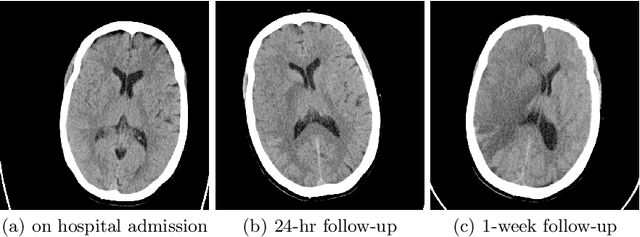

Abstract:Acute ischaemic stroke, caused by an interruption in blood flow to brain tissue, is a leading cause of disability and mortality worldwide. The selection of patients for the most optimal ischaemic stroke treatment is a crucial step for a successful outcome, as the effect of treatment highly depends on the time to treatment. We propose a transformer-based multimodal network (TranSOP) for a classification approach that employs clinical metadata and imaging information, acquired on hospital admission, to predict the functional outcome of stroke treatment based on the modified Rankin Scale (mRS). This includes a fusion module to efficiently combine 3D non-contrast computed tomography (NCCT) features and clinical information. In comparative experiments using unimodal and multimodal data on the MRCLEAN dataset, we achieve a state-of-the-art AUC score of 0.85.

Abstract:Recent randomised clinical trials have shown that patients with ischaemic stroke {due to occlusion of a large intracranial blood vessel} benefit from endovascular thrombectomy. However, predicting outcome of treatment in an individual patient remains a challenge. We propose a novel deep learning approach to directly exploit multimodal data (clinical metadata information, imaging data, and imaging biomarkers extracted from images) to estimate the success of endovascular treatment. We incorporate an attention mechanism in our architecture to model global feature inter-dependencies, both channel-wise and spatially. We perform comparative experiments using unimodal and multimodal data, to predict functional outcome (modified Rankin Scale score, mRS) and achieve 0.75 AUC for dichotomised mRS scores and 0.35 classification accuracy for individual mRS scores.